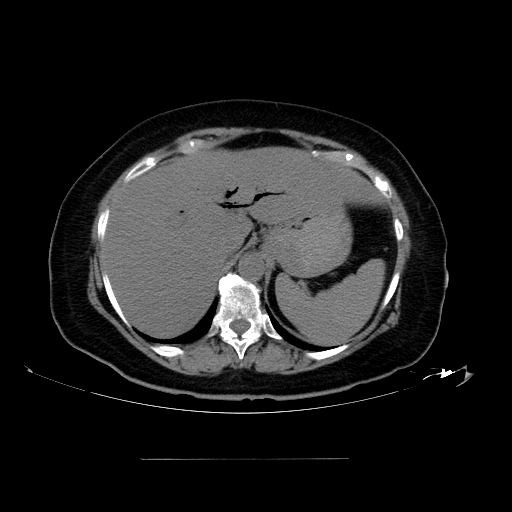

Porcelain gallbladder is a complication of late stage chronic cholecystitis.

Porcelain gallbladder is a shrunken, hard gallbladder because of chronic inflammation, fibrosis, and dystrophic calcification.

Porcelain gallbladder findings vastly increases the risk for carcinoma of the gallbladder.

Cholecystectomy is the recommended course of action for chronic cholecystitis, especially if a porcelain gallbladder is present.